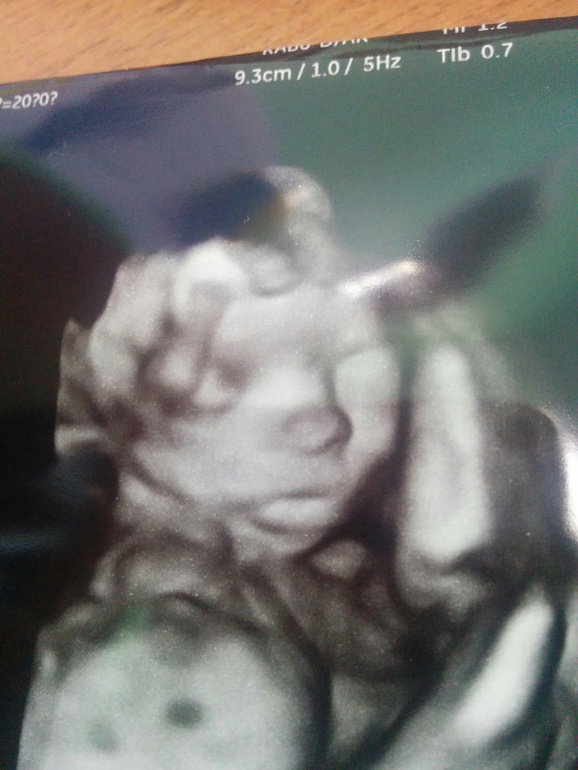

Я хожу на дневной стационар, капают магнезию... И защимляет седалищный нерв,жесть, встать не могу если лежу на спине((( Сегодня делали ЭКГ,сказали в норме,только сердцебиение должно быть до 80,у меня 89...терапевт сказала у меня на нервной почте до давление скачет, говорит пить перед приемом глицин. И коленно-локтевая поза мне от боли в спине... А так я пока на больничном хожу много на улице,воздух теплый, мне так хорошо!!! Голова не кружится!!!!))) А гемоглобин у меня 111,тоже сказали поднимать,но я не буду опять пить железо, от него мне тяжко в туалет ходить. Самое главное малышка такая милаха курносая, губастая,прям красотка!)))

Ой ты даже рассмотрела так хорошо доченьку...Ты на обычное ходила УЗИ или на 3D?Да главное, чтобы всё было с малышкой хорошо, а сердцебиение и давление у тебя реально уже от нервов. Я тоже иду к врачу и каждый раз думаю, ну что уже сейчас у меня всплывёт из бяки?...

Личико прятала руками постоянно,еое смогли сделать фото... 3д

Ой, какая мимимишность, ну настоящая девочка!!!Тут можно даже писюн не рассматривать!Тьфу-тьфу-тьфу на вас растите здоровенькими!